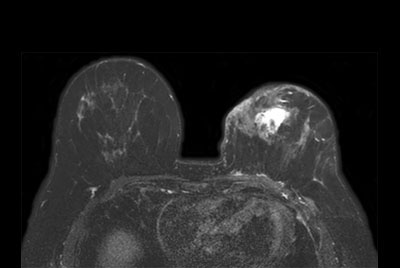

Breast Ca with T1 perfusion